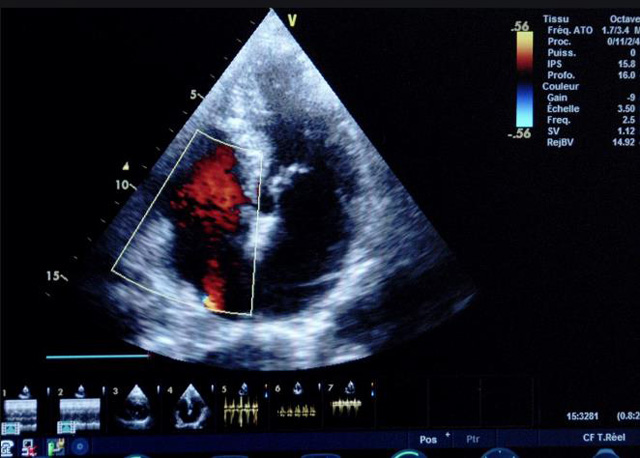

二、彩色室壁运动分析

(一)基本原理彩色室璧运动分析,从整体散射数据中识别心内膜边界,并与前一帧彩色不同,心脏收缩或舒张期开始到结束时心内膜的全部过程。每一次顺序显示结束后,原来的彩色自动消失,以便进入下一个显示过程。其结果是获得对应于每一个心动周期的彩色显示,描绘特定周期内室壁运动的时间运动轨迹。

(二)操作步骤根据背向散射数据中将心内膜运动的位移过程分类为组织或血液的原理,边缘检测跟踪心内膜和血液的界面。橙色表示收缩期的开始,收缩期不同时相逐帧显示色彩均叠加在收缩末期最后一帧图像中。检查时,可按以下步骤进行:

①显示较为理想的二维图像,常用切面有心尖四腔心、二腔心、左心室长轴和左心室乳头肌水平短轴切面。

②启动AQ系统,启动后适当地调节增益补偿,显示心内膜。

③启动CK系统,启动后划定感兴趣区域。同时记录的心动图R波顶点为舒张末期,T波终点为收缩末期,显示RT间期的CK彩阶图,连续记录3~ 5个心动周期。